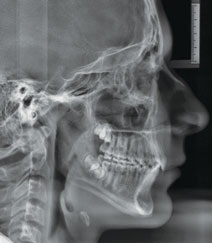

Figs. 3a-g: Initial records.

Fig. 3a

Fig. 3b

Fig. 3c

Fig. 3d

Fig. 3e

Fig. 3f

Fig. 3g